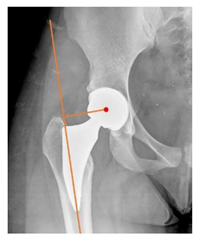

Plain radiographs were evaluated preoperatively and at the most recent follow-up, after appropriate calibration. Positional parameters were assessed according to values guidelines from published literature, as listed in Table 1 [23,24,25,26,27,28,29,30,31]. Femoral stem and acetabular cup osteointegration were quantified according to Engh [32] and Moore scale [33]. Heterotopic ossifications were graded according to the Brooker system [34].

3.4. Radiographic Evaluation

Preoperative and postoperative radiographic data are reported in Table 4. Preoperatively, 18 THR (24.3%) were implanted in skeletally immature children with closed triradiate cartilage (1 ≤ Risser ≤ 3). Radiographic acetabular insufficiency (LCEA < 25° and AI > 13°) was detected in 14 hips (18.9%), while protrusion was present in 3 hips (4.1%) An excessive valgus of the femoral neck was observed in 19 hips (25.7%), while an important varus deformity was present in 7 hips (9.5%).

Preoperative and postoperative radiographic parameters. All results are expressed as crude numbers for dichotomous variables and as mean ± Standard Deviation for continue variables. LCEA: Lateral center-edge angle. * Varus inclination is expressed as negative value, positive value for valgus.

Postoperative radiographs showed a significant vertical malposition of the cup in 1 case (1.4%), a significant varus stem in 8 cases (10.8%) and a significant valgus stem in 1 case (1.4%). Two patients (2.7%) showed moderate heterotopic bone formation (Brooker ≥ 2), that did not significantly affect the hip motion and symptoms. All those THR that did not undergo revision showed good radiographic osteointegration, with no evidence of implant breakage, radiographic lucencies, bone defects, cup migration, or stem subsidence at the most recent radiographs.

In our experience, implant malposition was the only reason for implant revision. In one case, progressive subsidence was observed in a varus undersized stem, implanted in a boy with Albers–Schömberg disease; in another case, an excessively vertical cup with a 28 mm femoral head caused hip instability and required cup revision.

THR can be a challenging procedure in very young people. The combination of distorted anatomy, small physique, and poor bone stock can impede proper implant placement. Implant sizing may be an issue in these patients. The combination of young age and peculiar conditions such as skeletal dysplasia may require particular attention in preoperative planning and implant selection. Noticeably, we used the smallest size of the cup in 11 hips (15%) and the smallest size of the stem in 14 hips (19%). A meticulous preoperative planning, even using simulation software, [40,41,42] and careful implant selection, sometimes requiring even customized implants [37], is crucial in such conditions, to prevent unpleasant pitfalls during the operation.